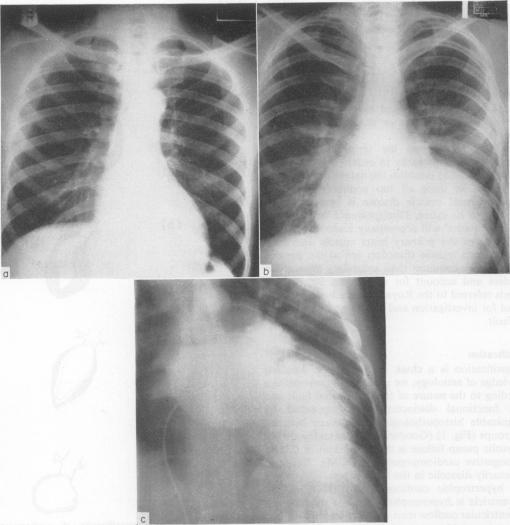

Postgrad Med J. 1975 May;51(595):271-6. doi: 10.1136/pgmj.51.595.271.